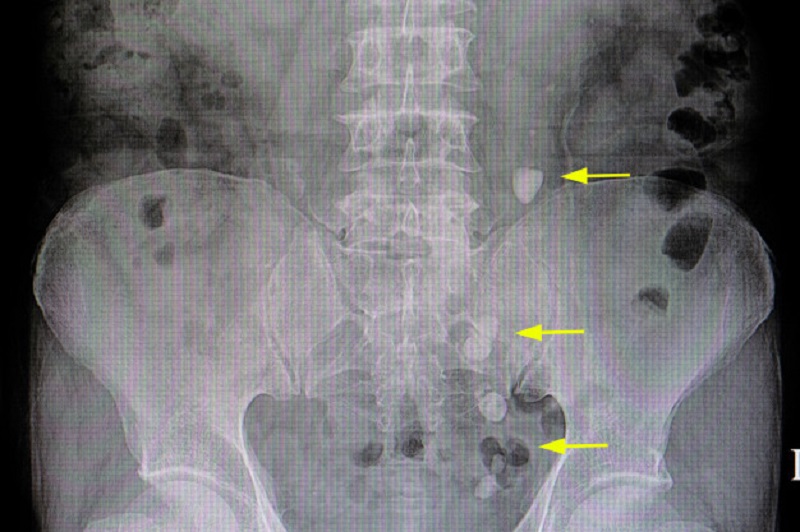

Cơ quan thận cũng bị ảnh hưởng lâu dài nếu như ăn mặn quá nhiều. Trong đó thì phổ biến là tình trạng sỏi thận, nó sẽ xảy ra khi trong nước tiểu khoáng chất như canxi bị cô đặc lại trở thành tinh thể. Có thể phát triển lớn hơn theo thời gian khi thông qua đường tiết niệu, tại đây có thể bị mắc kẹt, dẫn tới việc bài tiết nước tiểu bị cản trở, chức năng thận suy giảm làm suy thận, sỏi thận,...